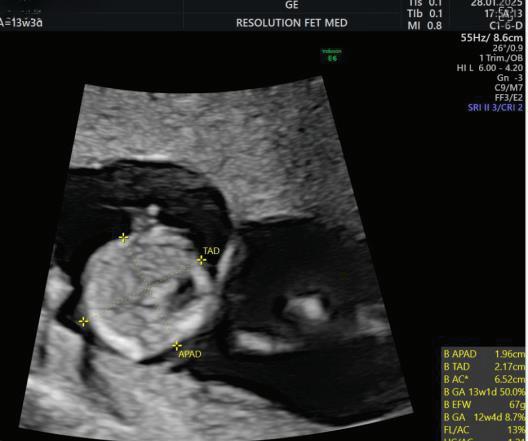

MEASUREMENTS THAT CAN BE OBTAINED ON

First Trimester Fetal Evaluation:

FETAL ULTRASOUND EXAMINATION AT 11 TO 14 + 0 WEEKS: BASIC BIOMETRY INCLUDES:

Nuchal Translucency

Biperital Diameter

(a) Crown Rump Length(CRL)

(b) Biperital diameter(BPD)

(c) Nuchal Translucency(NT)

DETAILED BIOMETRY INCLUDES:

Along with basic biometry

(a) Abdominal circumference

(b) Head circumference

(c) Femur length

Abdominal Circumference